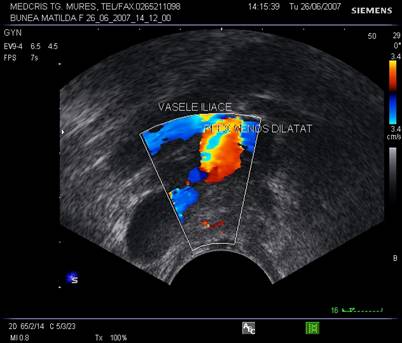

Fig. nr.395.Plex venos dilatat , parametral ( diagnostic diferential cu un chist ovarian, dificil uneori , la ecografia transvaginala )

Fig. nr.396. La ecografia tranvaginala asociata cu Doppler , plexul venos dilatat se diferentiaza facil de un chist ovarian